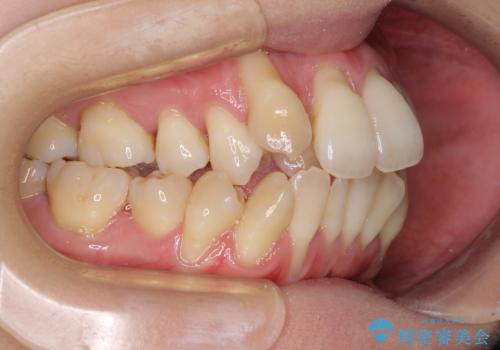

急速拡大装置 狭い骨幅を拡大した上で、顕著なデコボコを改善する抜歯矯正治療

- 前歯のデコボコと唇の閉じにくさを気にして来院された患者様です。

上顎骨よりも下顎骨の幅が広く、更には下顎骨が左側に変位していたため、より良い咬み合わせを達成することを目的として、急速拡大装置を用いて上顎骨を拡大することとしました。

デコボコが強い上に、口元の突出感も気にしていたため、上下左右の小臼歯4本を抜歯して、ワイヤー装置にて矯正治療を行うこととしました。